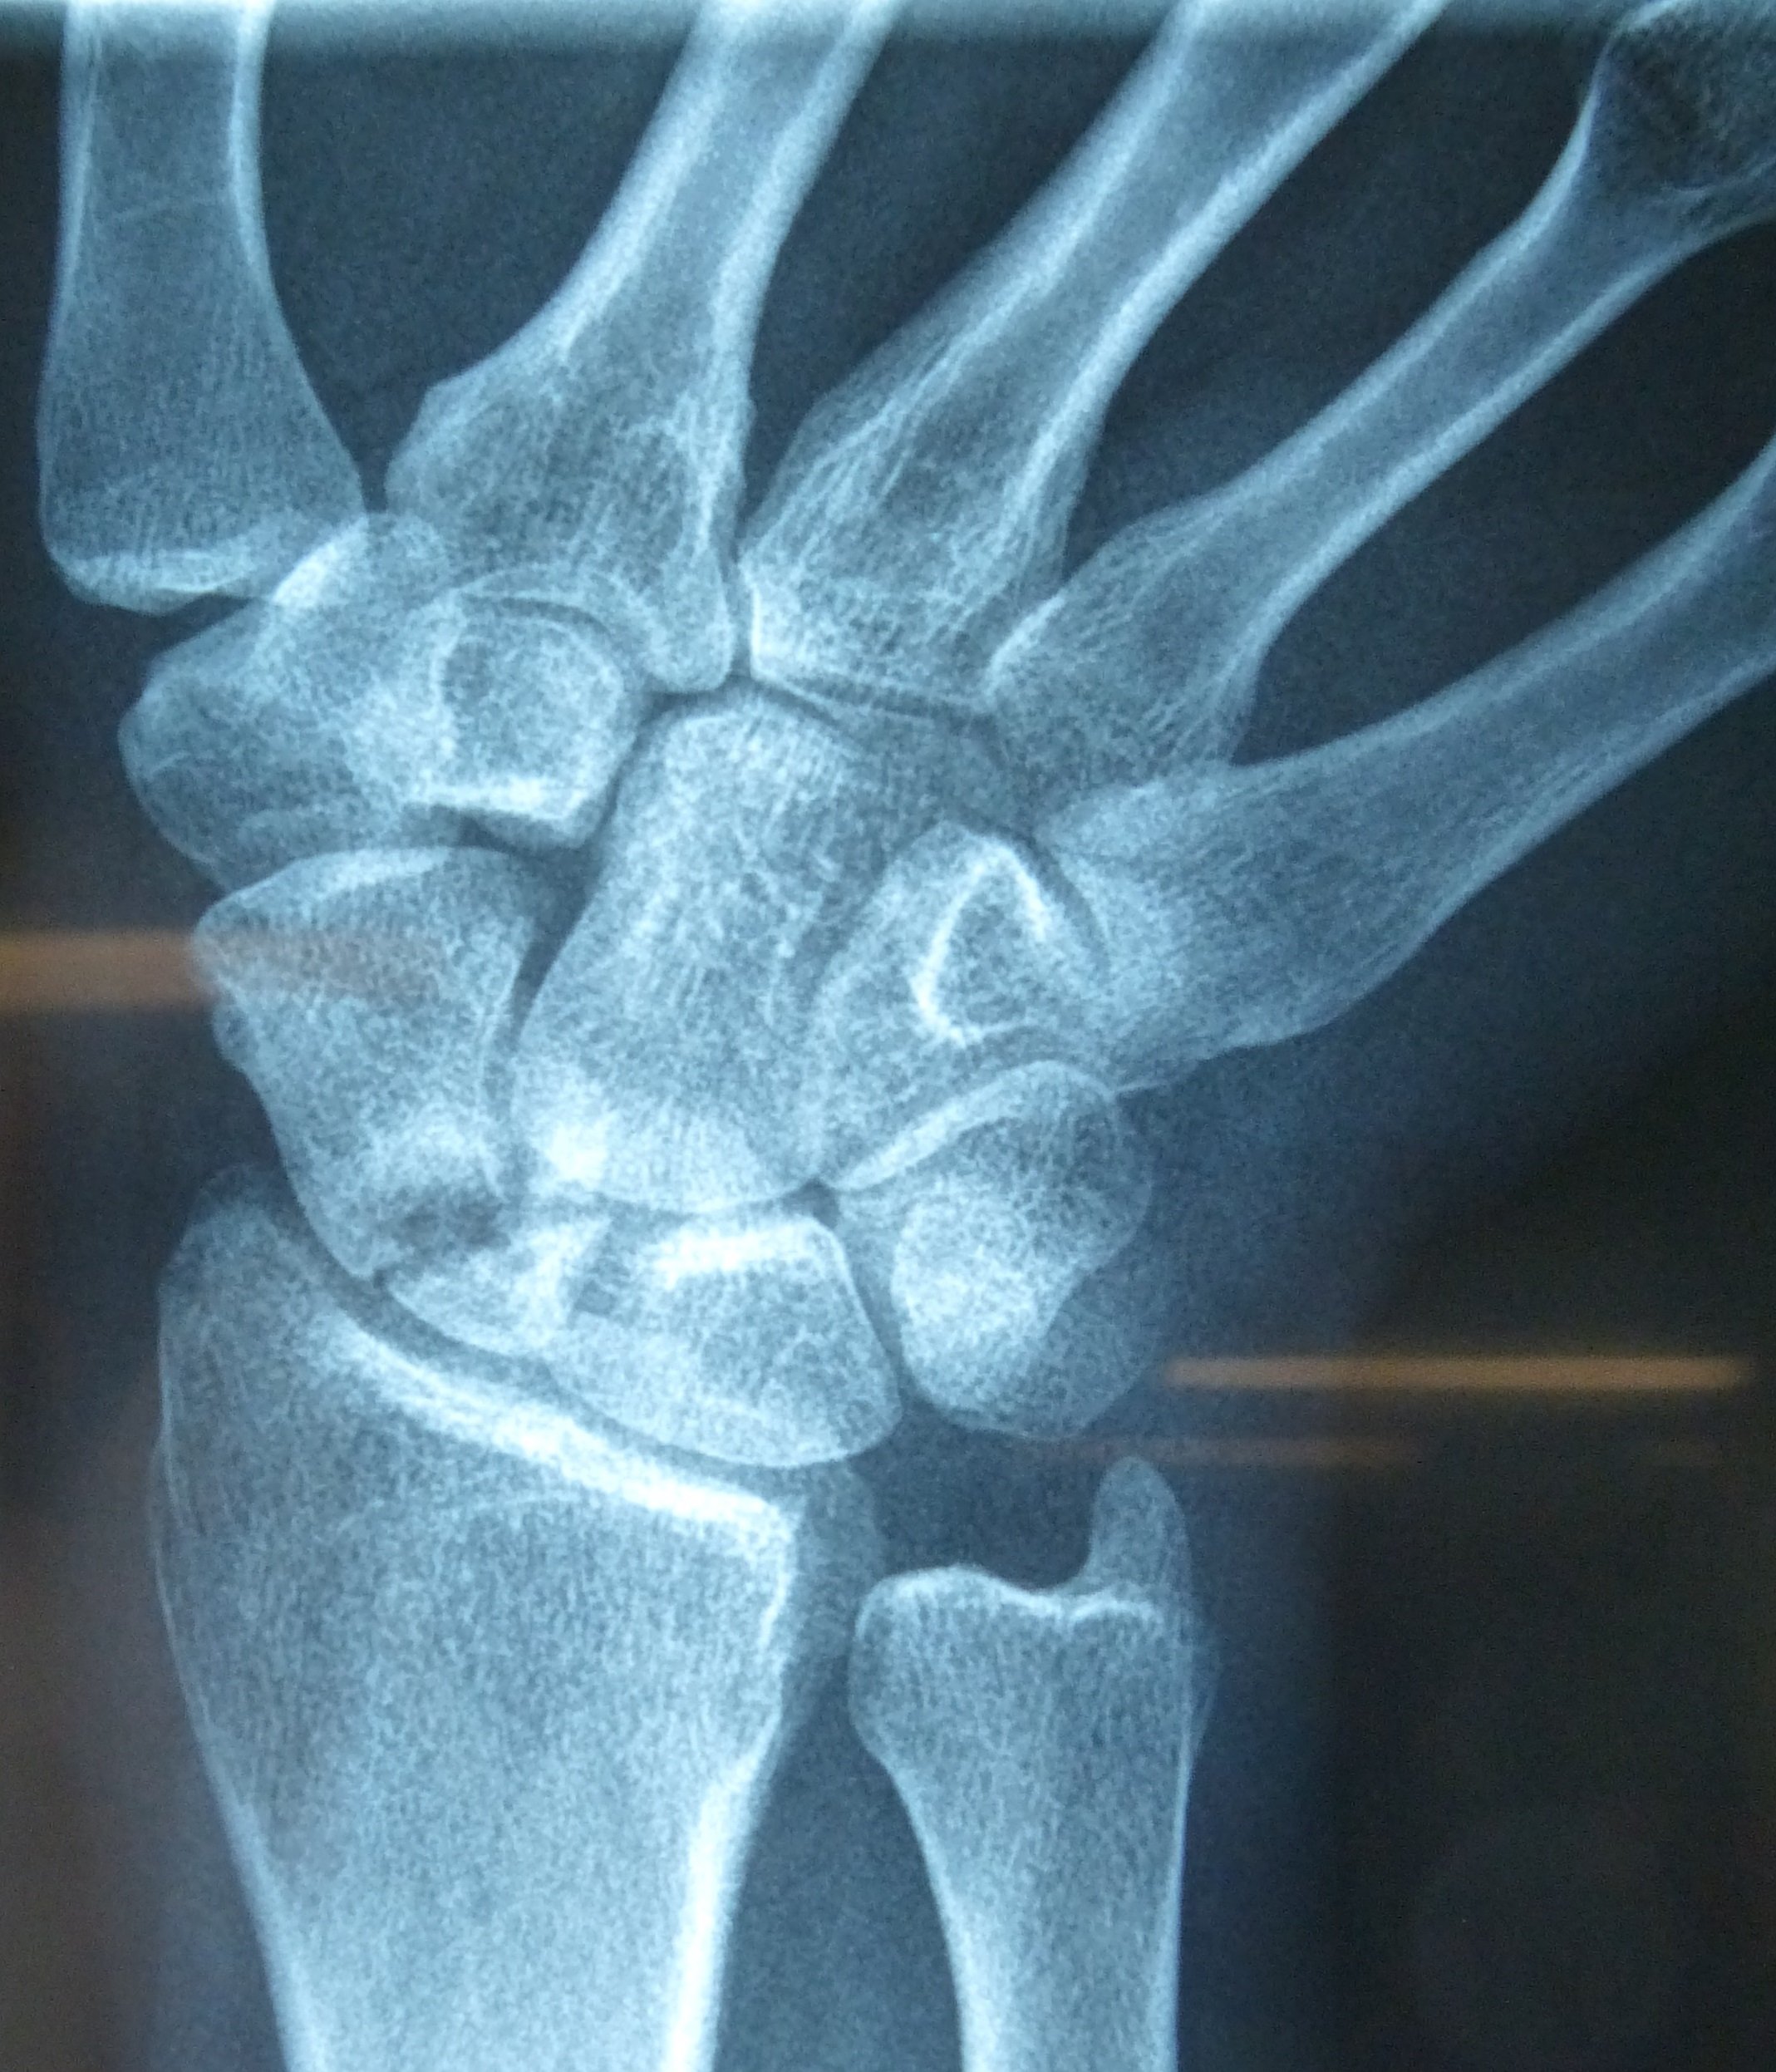

Η ψευδάρθρωση καταγμάτων του σκαφοειδούς δεν είναι σπάνια επιπλοκή (βλ αντίστοιχο κεφάλαιο). Λόγω ανατομικών και φυσιολογικών ιδιαιτεροτήτων του σκαφοειδούς ή λόγω υποτίμησης των ενοχλημάτων εκ μέρους του αρρώστου, το κάταγμα συχνά διαφεύγει της αρχικής διαγνώσεως. Αυτό οδηγεί σε ανεπαρκή αντιμετώπιση, η οποία καταλήγει σε μη πώρωση (ψευδάρθρωση) του σκαφοειδούς. Η κατάσταση αυτή αρχικά έχει ελαφρά ή καθόλου συμπτώματα, με την πάροδο όμως των ετών εγκαθίσταται προοδευτικά επώδυνος περιορισμός της κινητικότητας του καρπού και ελάττωση της δύναμης δραγμού (αδύναμο σφίξιμο σε γροθιά).

Οσο κοντύτερα προς τον αγκώνα είναι το κάταγμα (κατάγματα του κεντρικού πόλου) τόσο μεγαλύτερη είναι η πιθανότητα να εμφανισθεί και νέκρωση του κεντρικού πόλου λόγω διακοπής της αιμάτωσης (άσηπτη νέκρωση). Αυτό καθιστά ακόμη πιο δύσκολη τον χειρισμό της ψευδάρθρωσης.

Προεγχειρητικά